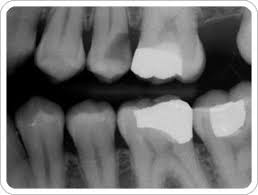

| ha..lebih kurg camnila x-ray 2..tp ak x-ray atas je..bwh x... |

so kt cni ak nk kongsi skit tips yg dentist ak bg after cabut gigi or minor surgical. nmpk skit ak nih bpengetahuan..bkn Dr DM je leh bg tips ye..

- kena gigit kapas kuat-kuat so that darah x kuar bnyk selama 1/2 jam..ala cam bile korg luke kena pisau ke ape ke..korg akan tekan tmpt kuar darah 2 bg darah x bnyk kuarkn...kalo darah still bnyk..tukar ngan kapas yg baru..

- mase ubat bius 2 mmgla korg x rase pe..kalo org tampar laju2 pon bknne korg rase tp jgnla gigi tmpt yg kena bius 2..abih kesan..mmg padan muke korg..

- jgnla gatal dok usik2 tmpt yg kena cabut ok..give some space..

- jgn lalu aktif/ lasak..mmg kena tang batang hidung ak sebijik..mmg x brutalla..

- Amik ubat ikut arahan..kt ubat ak tulih amik bile perlu..so, ak pon x tau bile perlu 2 camne..

- bnyk minum air..yes..mmg airla penyelamat ak...

- bile nk tdo, tinggikn bhgn pale..mmg bkesan..ak dh try dh,,nyenyak ak tdo n sakit pon x trase sgt

- jgn kumur2, ludah2 dgn kerap n amik mknn n minuman panas..memula 2 ak pelik gak..coz apsal x leh kumur..lidah ak dh loya dh ngan darah2 nih..tp..(hehe..smpai skank ak x tau nape)

- after dh sehari barula kumur ngan air suam campur garam or ubat kumur yg halal..so that cpt skit baik gusi korg 2..

- kalo gusi korg masih lg berdarah...kapas pon dh x de...jgn risao..cari handkerchief yg bersih, lipat kecik2 n gigit kuat-kuat...

- pas2 gigit pelan2 kain bersih yg diisi ketulan ais..ketulan ye..pecahkn skit2..

- kalo masih x baik...pegila jumpe dentist di Klinik Pergigian yg berhampiran...jgn mengedik kt parents ke..kengkwn ke..bf ke..bknnye diorg leh wat pape..lenla kalo diorg 2 dentist or yg sewaktu dgnnye...hehe...